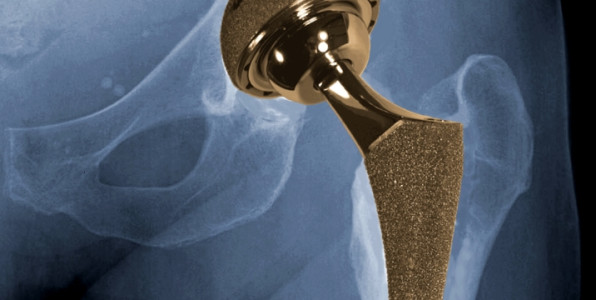

Hip Replacement

Hip replacement devices have increased in popularity over the past two decades. This is because new innovations, especially metal-on-metal designs, have promised increased mobility. But in 2010, Depuy Orthopaedics’ hip replacement recall brought attention to potentially serious injuries from these devices. The company reportedly spent $800 million on the recall.